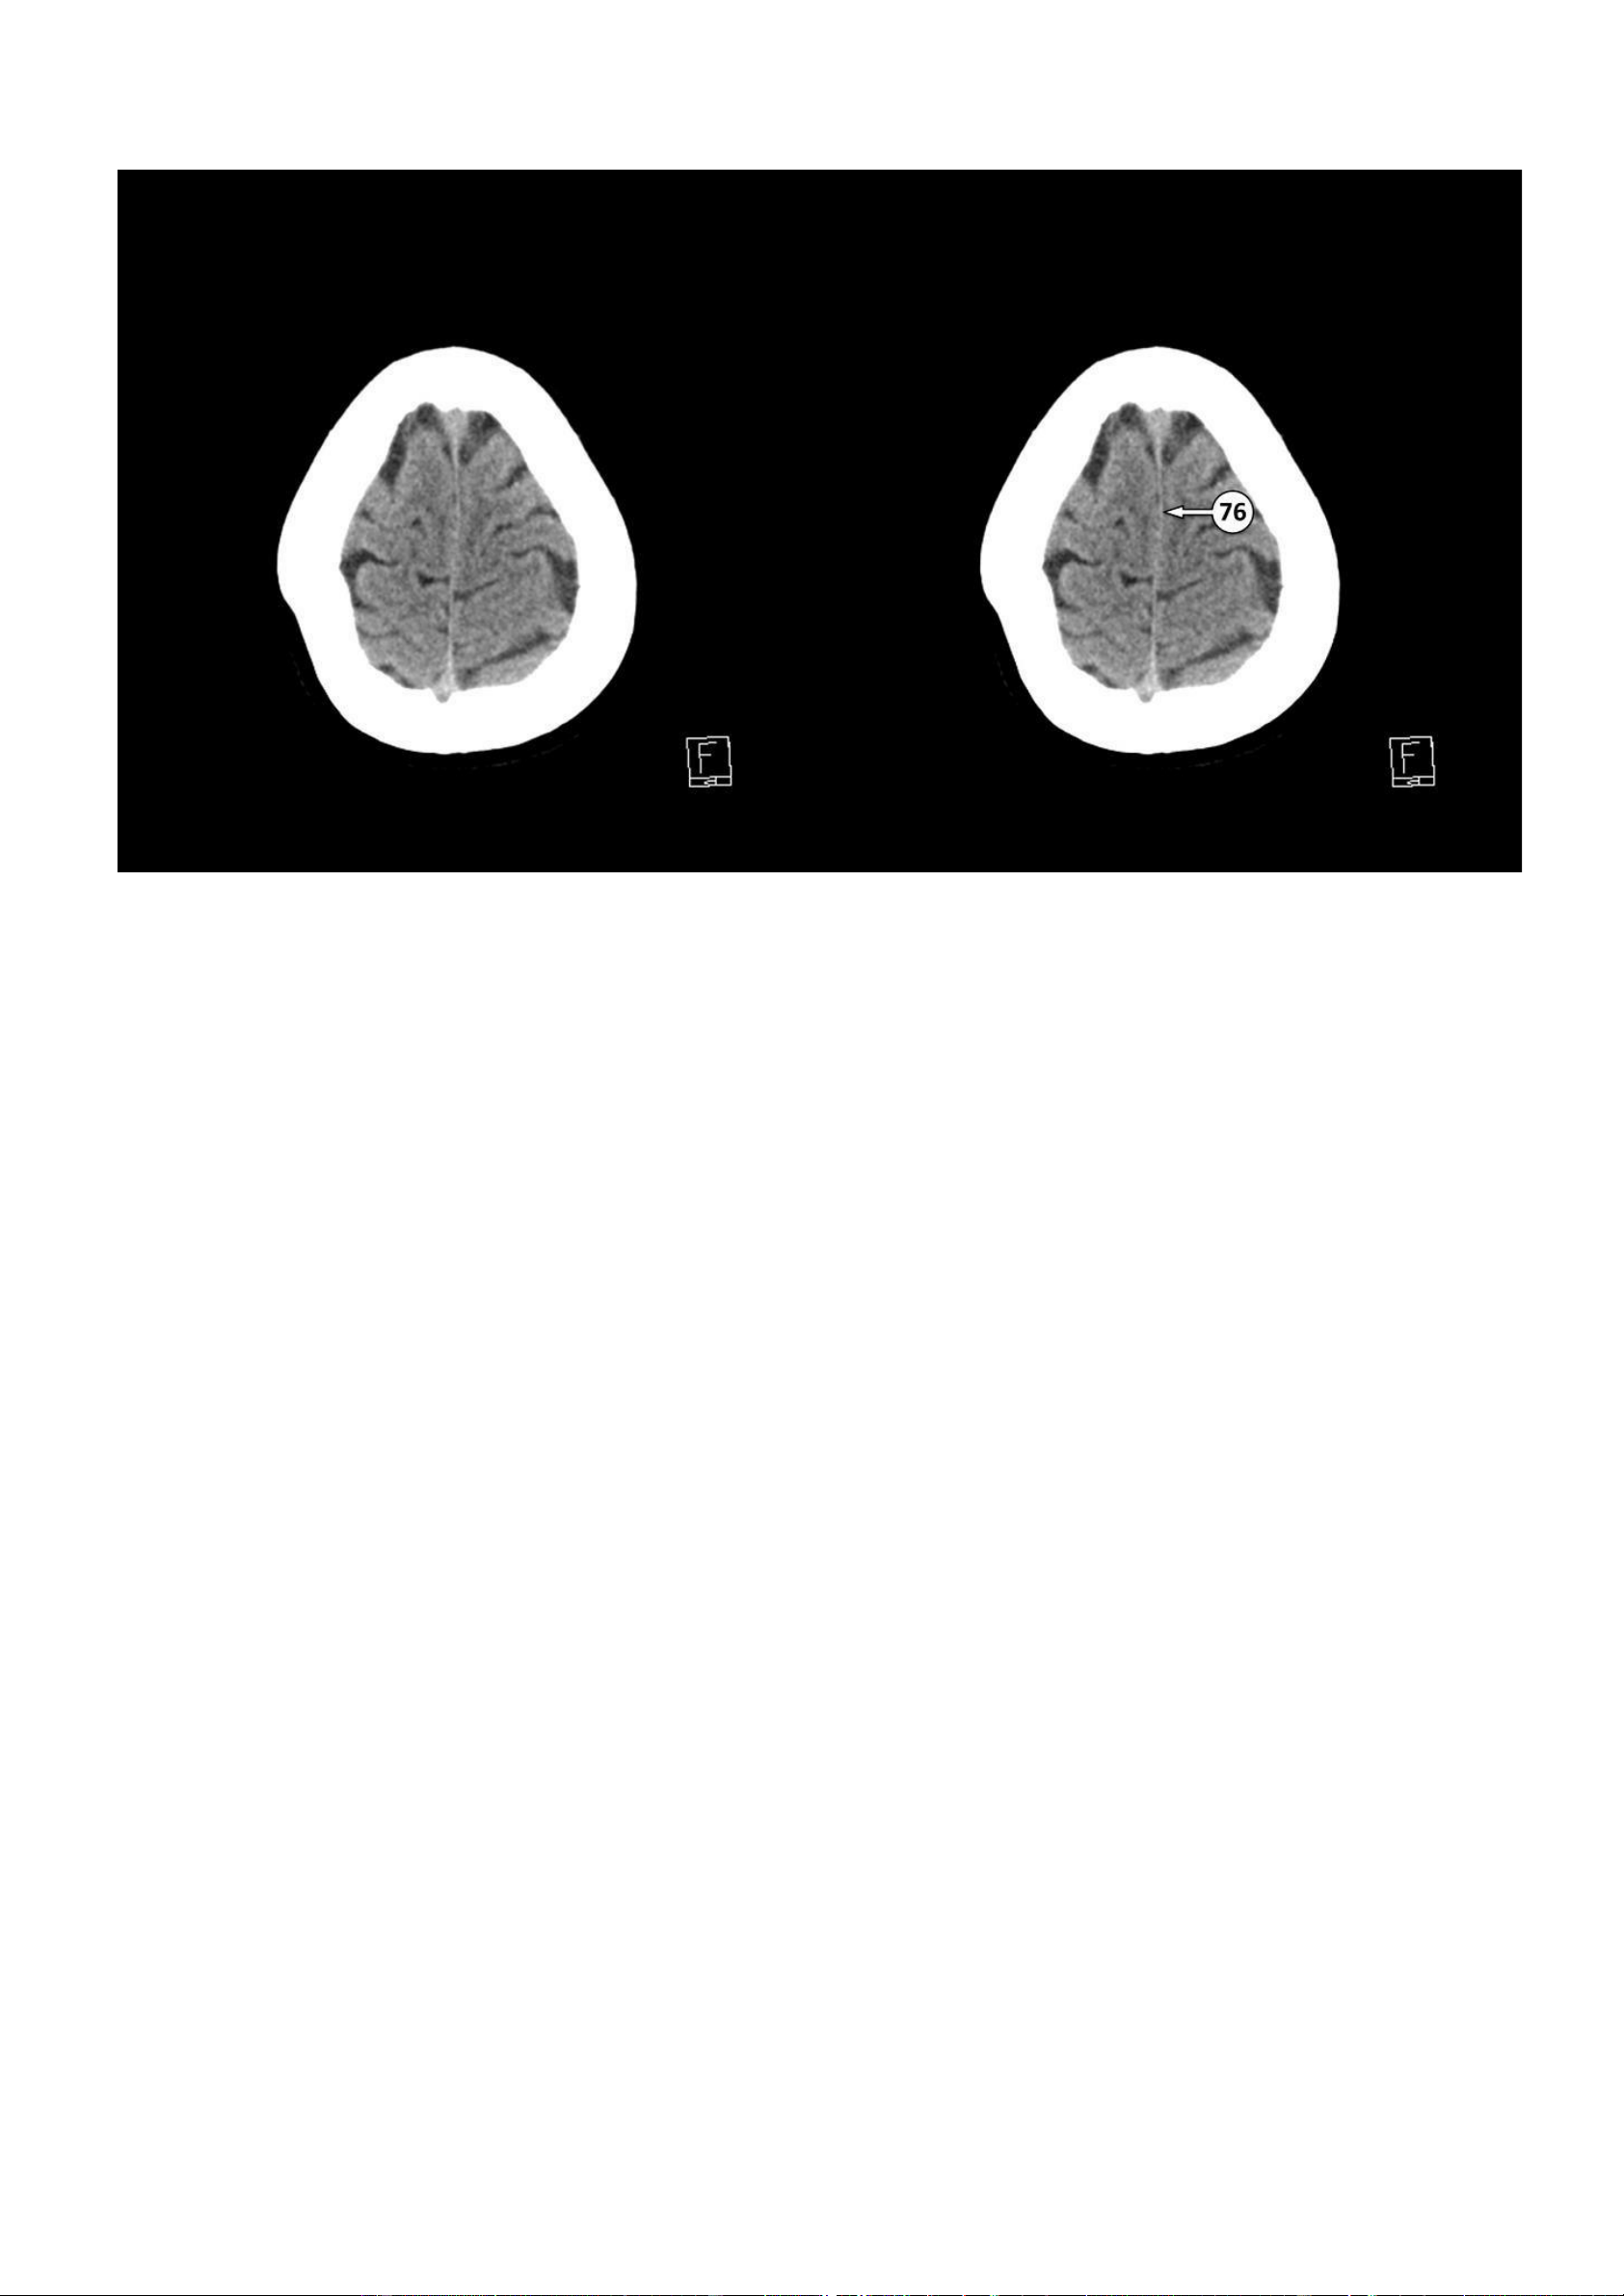

▪ Số 76: Liềm đại não lOMoAR cPSD| 22014077